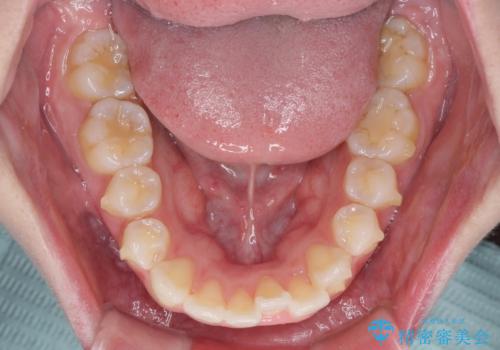

抜歯矯正の後戻り インビザラインによるオープンバイトの再矯正

- 以前矯正治療をされていましたが、後戻りが起きたことを気にして来院された患者様です。

上下前歯のオープンバイトを改善するため、インビザラインにて治療を行うこととしました。

外食が楽しみである患者様だったので、インビザラインによる治療期間は我慢の時期であったようです。

自己管理を徹底していただいたので、1年程度で治療を終えることができました。